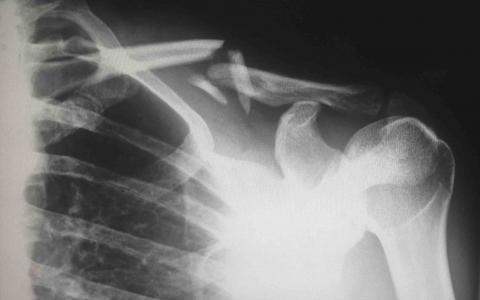

Serious back injuries can result from car accidents, activity at work, or from a slip and fall at a place of business such as your local supermarket or post office. The lower back is the most common site of back injuries and back pain. Common back injuries include:

- Strains and Sprains,

- Herniated or Bulging Discs, and

- Fractured Vertebrae

Back injuries are the most common reasons for missed work. Possible long-term effects of an untreated back injury include paralysis of the lower back, chronic pain, prolonged suffering and discomfort, and loss or impairment of movement. Many times, what is initially considered a minor accident can result in damage to the muscle, bone, the spinal cord, or the discs between the vertebrae.